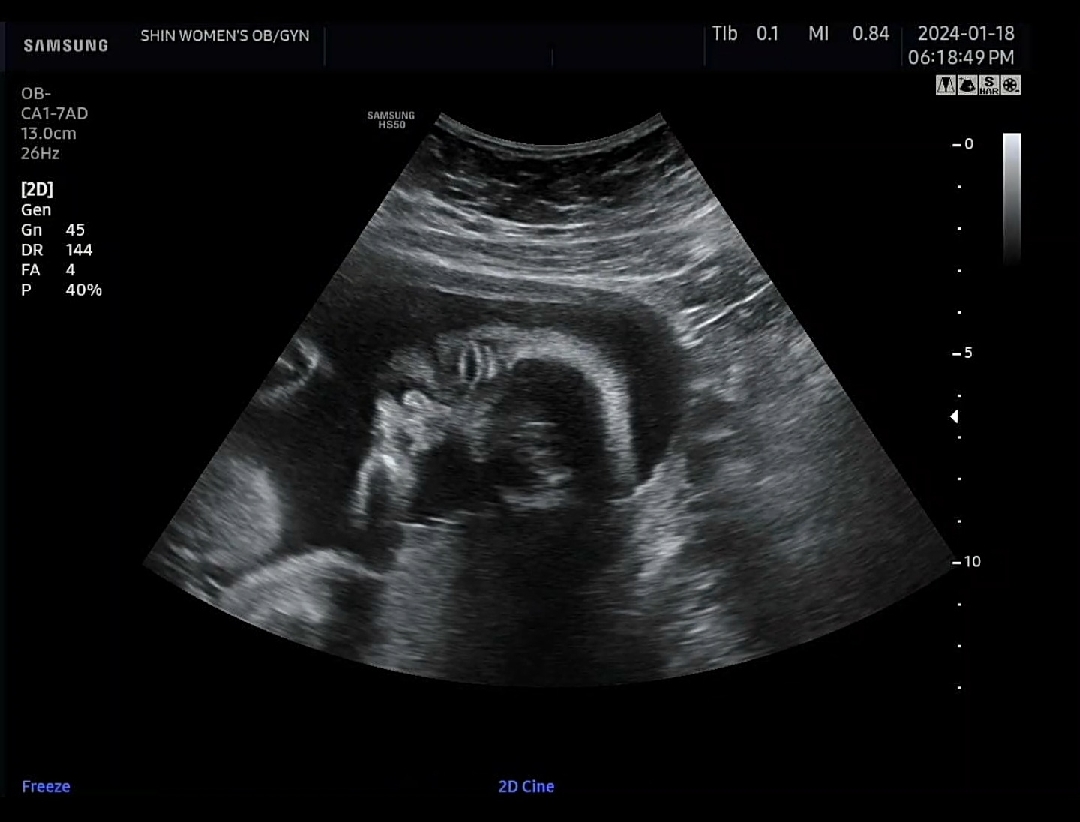

초음파에서 눈뜬거 볼때마다

저만 무섭나여....? 신랑은 엄청 신기하다하는데 약간 전 무섭더라규요 ㅎㅎ 그래도 건강하게 잘 자라고 있어서 맘을 좀 놓아요

엇 !저게 뜬거구나ㅋㅋ 신기하네요

우와! 눈 뜬 초음파 처음 봐요. 신기해요 👀 제가 있는 곳은 딱 두 번만 초음파 봐주는데 다행히(?) 제가 수술이력이 있어서 30주에 한 번 더 가요. 저도 눈 뜬 거 보고싶네요 😆